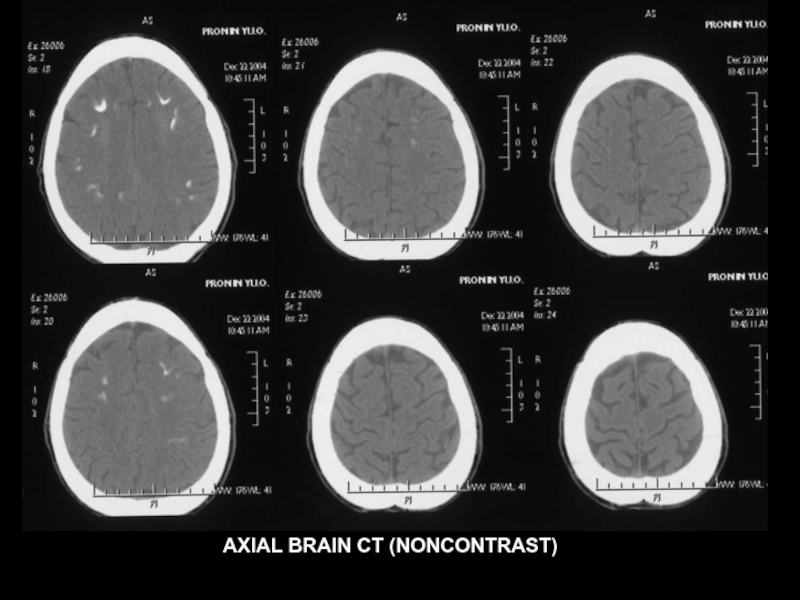

AXIAL BRAIN CT (NONCONTRAST)

Слайд 36Болезнь Фара

Болезнь Фара (семейная кальцификация базальных ганглиев, идиопатический кальциноз мозговых сосудов)

- наследственное заболевание, характеризующееся симметричной кальцификацией сосудов и вещества головного мозга, прежде всего в области базальных ганглиев и мозжечка. В тяжёлых случаях кальцификации подвергаются таламус, кора больших полушарий, подкорковое белое вещество.

Клинические проявления

1.Паркинсонизм

2.Деменция

3.Мозжечковая атаксия

4.Эпилептические припадки,